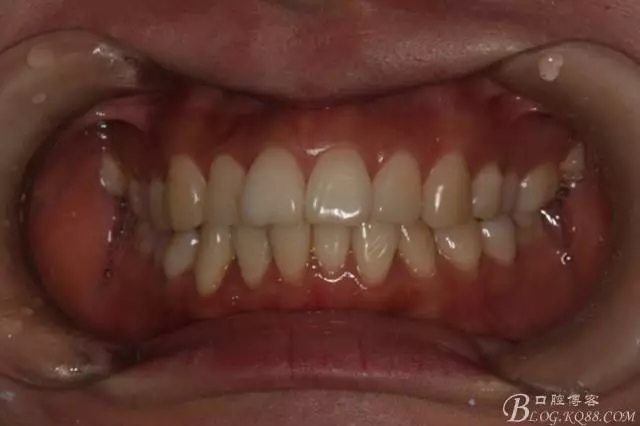

患者,女,主訴:牙齒不齊。

如圖,該病例為簡單排齊病例,但77鎖合是矯治中的關鍵所在,你會怎么處理?

該病例主要為17、27頰側(cè)位同時伴有伸長,當然種植支抗可以解決,但還有簡單實用的辦法嗎?如圖,在橫腭桿遠中延伸出牽引鉤,位置盡量遠離合平面,7粘舌側(cè)扣,牽引力的方向為壓低及舌向,下圖為兩個月的效果,17已到位,27還未到位。